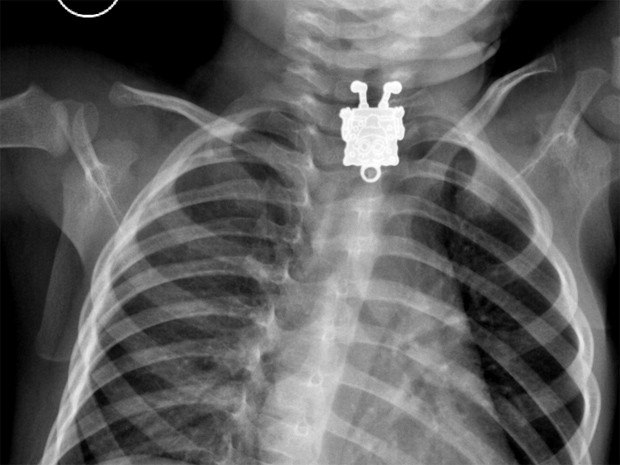

Médicos da Arábia Saudita se surpreenderam ao examinar um raio-X de um garoto de 1 ano e 4 meses que aparentemente tinha se engasgado com um objeto.

Um Bob Esponja pôde ser visto com riqueza de detalhes no esôfago do paciente. O objeto foi retirado pelos médicos sem complicações e o garoto passa bem.

O personagem de desenho animado era, na verdade, um pingente que pertencia à irmã mais velha do menino.

A médica conta que o primeiro raio-X, tirado do corpo de lado, mostrou um pequeno objeto que os médicos pensaram ser um grampo ou outro acessório de cabelo.

A radiografia frontal, porém, mostrava claramente do que se tratava: "'Bob Esponja', eu gritei! Fiquei impressionada com os detalhes visíveis. Você podia ver as sardas, sapatos e dedos. Incrível",

Os médicos tiraram o pingente do esôfago do garoto e o liberaram para ir para casa no mesmo dia.